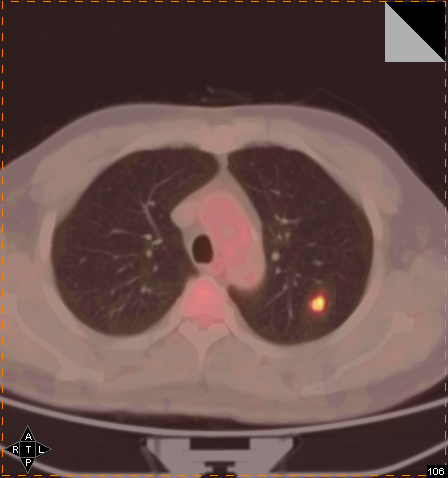

早期癌症筛查可以选择PET-CT。

PET可通过病灶的异常功能代谢情况来判断疾病,但不能提供某些病灶的准确解剖位置,也就是说:我知道有这个病,但未必知道病灶在哪里。CT 可以准确描述病变的形态、大小、和位置。但是只有当疾病发展到“形态改变”这一阶段才能被发现 ,不能达到“早期诊断”的目的。也就是说:我知道病灶在哪里,但往往是已经晚了一步。

正所谓强强联合,PET-CT便应运而生了,它综合“爹妈”的精华,在早期诊断肿瘤方面发挥了巨大作用。能够提早诊断并治疗,才可以把癌症扼杀在摇篮里。在精准医学的时代,疾病的诊治不仅要依赖组织形态和病理学基础,而开始更多地深入到分子水平。而PET-CT就是这一方面的强者。它的精准性可以发现尚且处于微小状态的肿瘤,更可以深入分子水平,反映病变组织代谢及功能状态,是精准医学时代不可或缺的工具。